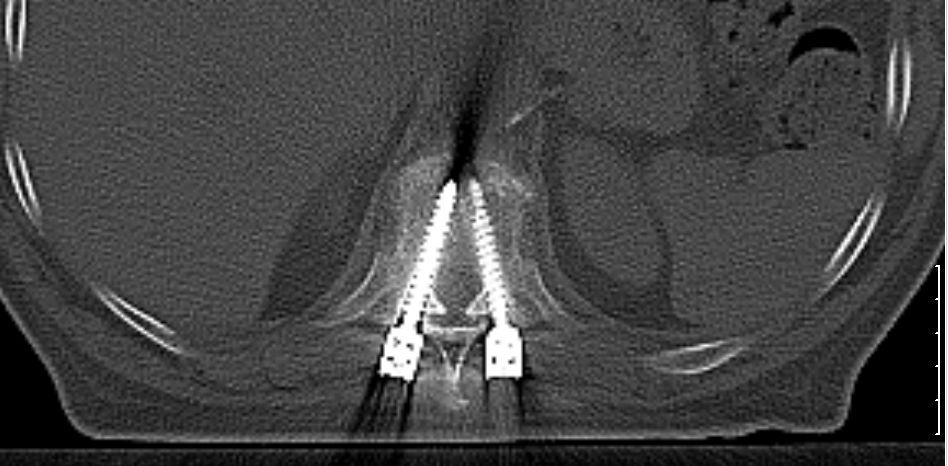

| Pedikel - Schrauben |

Pedikelschrauben in Th10 bei Plasmozytom in Th9.